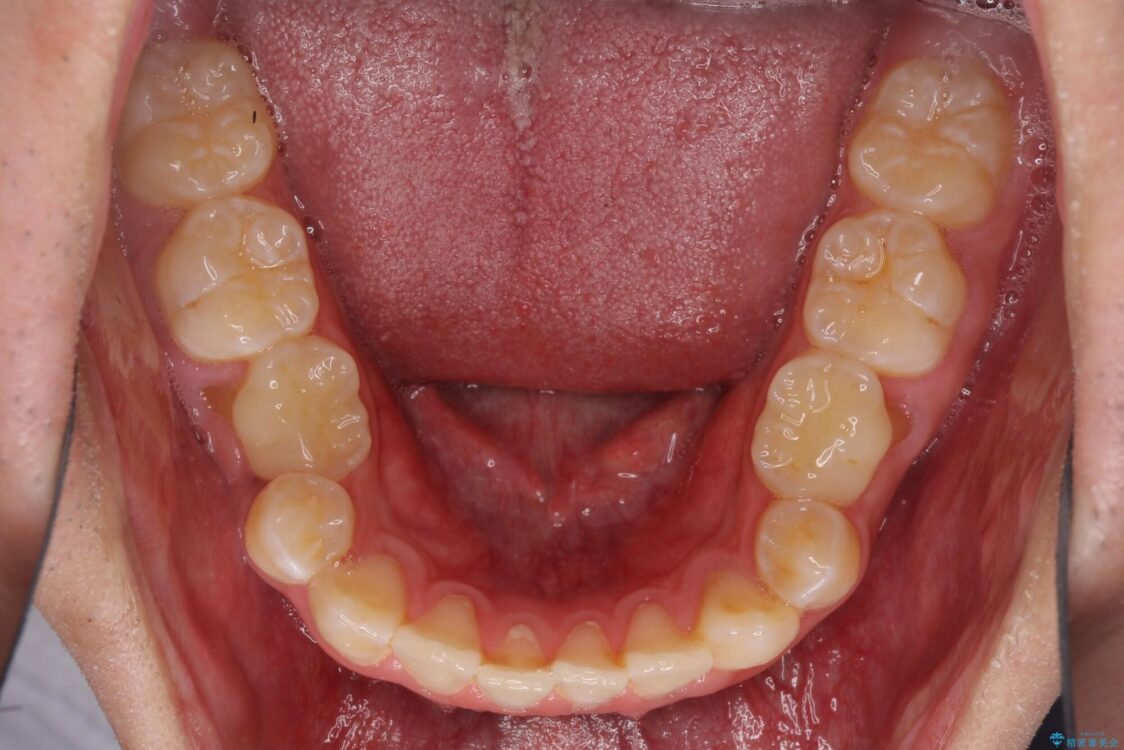

治療前

• 口元の突出感を改善 受け口傾向の咬み合わせの抜歯矯正 治療前画像